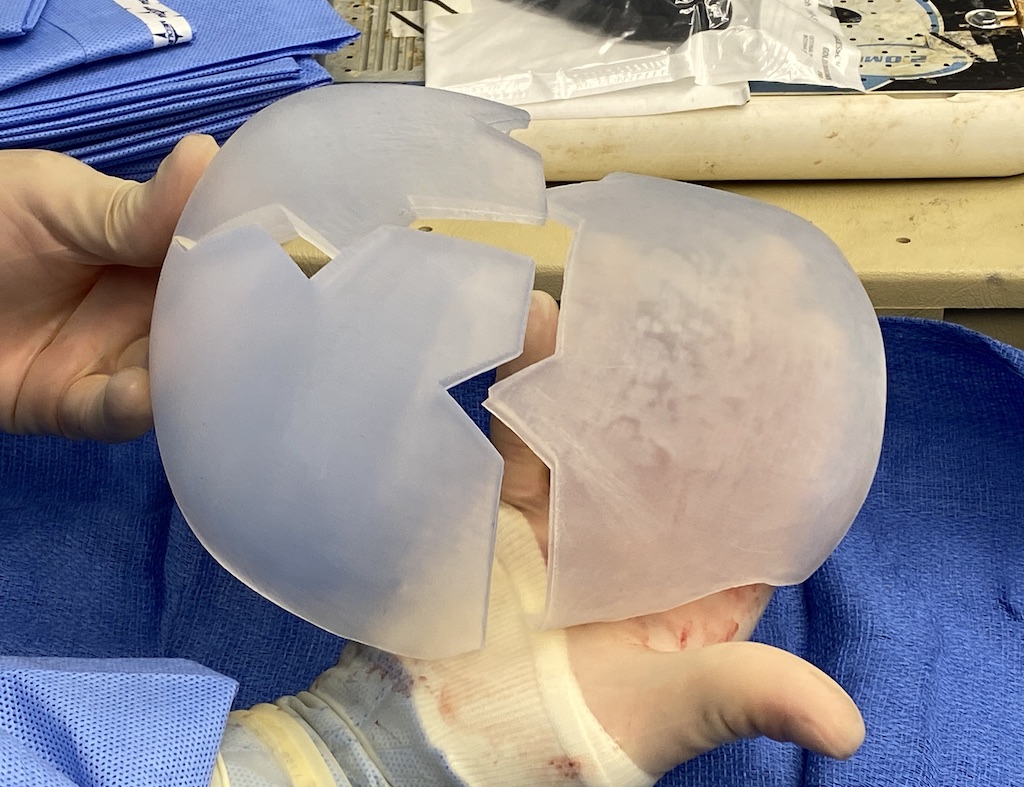

Desire for major head reshaping with a taler and wider head shape.

Placement of large two piece custom skull implant through a sagittal scalp incision.

Desire for major head reshaping with a taler and wider head shape.

Placement of large two piece custom skull implant through a sagittal scalp incision.